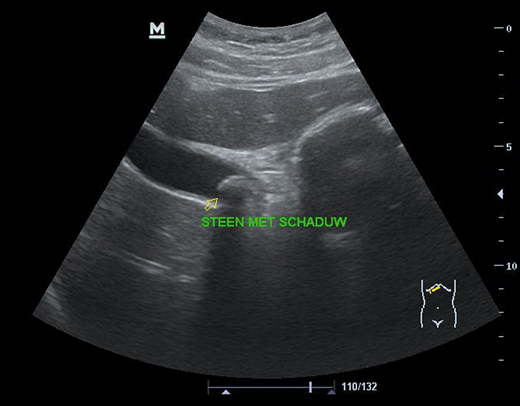

Een echoapparaat in de huisartsenpraktijk was tot voor kort een zeldzaamheid, wat vooral te maken had met de hoge kosten en forse afmetingen. Sinds een aantal jaren zijn betaalbare en compacte echoapparaten echter ruimschoots beschikbaar. Zelfs kleine handheld-apparaten die met een smartphone zijn verbonden behoren tot de mogelijkheden. Met echografie heeft de huisarts een belangrijk diagnostisch instrument in handen.